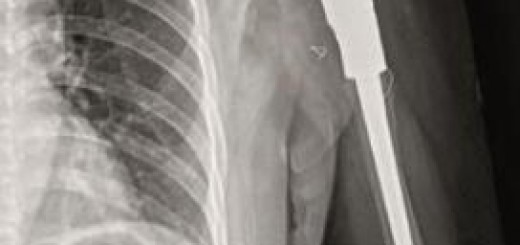

患者身高148cm,双下肢严重畸形,左侧明显(图1)。右膝关节屈曲挛缩,右膝活动度120°-25°-0°。2019年10月行左股骨、胫骨截骨矫形+术后缓慢撑开延长术(图2)。2020年11月23日行右股骨、胫骨微创截骨三维精准矫形+外固定术(图3)。术后1年余左股骨、胫骨正侧位片显示左股骨延长区域愈合、胫骨延长区域有明显骨痂生长(图4),左下肢延长12cm,遗留左小腿外旋畸形,(图5),采用3D打印个性化外固定支架非手术矫正(图6)。